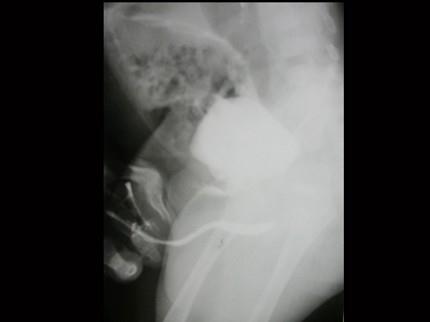

问题 男,4个月,阴茎、排尿异常4个月,行尿道造影如图所示,最可能的诊断是?(?)

选项 A.正常尿道 B.尿道瓣膜形成 C.尿道下裂畸形 D.尿道憩室 E.尿道重复畸形

答案 E